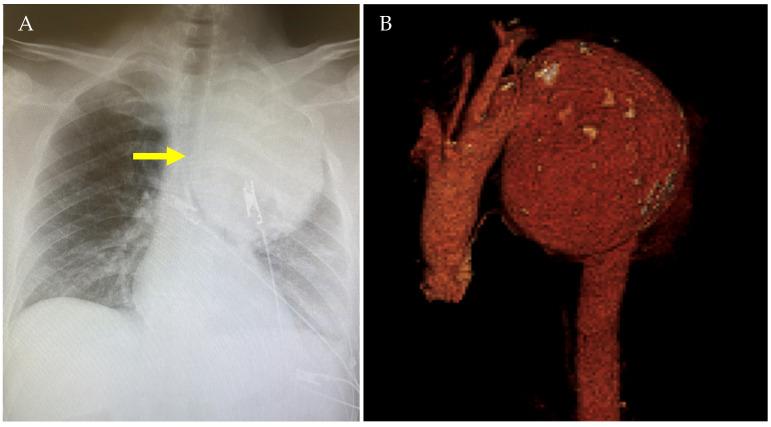

Grade I-II blunt traumatic aortic injuries (BTAIs) are typically managed conservatively, but their long-term progression is poorly understood. Chronic pseudoaneurysms may develop years after the injury, often remaining asymptomatic and being incidentally diagnosed. Two cases of post-traumatic aortic pseudoaneurysms, detected 20 and 25 years following conservatively managed BTAIs, are reported. Additionally, a comprehensive review of all post-traumatic pseudoaneurysms reported in the MedLine (PubMed.gov, U.S. National Library of Medicine, National Institute of Health) database between January 1984 and December 2024 was performed. Both our patients underwent successful hybrid procedures, with no complications at the 1- and 4-year follow-ups. Our literature review identified 37 patients across 22 studies, with 32.4% presenting asymptomatically or incidentally diagnosed through routine imaging, between 1 month and 50 years after the initial trauma. In 37.8% of cases, the patients underwent open or endovascular repair. This case series and literature review emphasize the importance of long-term follow-up for patients with conservatively managed BTAIs, as chronic complications such as aortic pseudoaneurysms can arise decades later. Continuous surveillance is critical to ensure early detection and management.

I-II级钝性创伤性主动脉损伤(BTAIs)通常采用保守治疗,但其长期进展情况尚不清楚。慢性假性动脉瘤可能在损伤数年之后形成,常常没有症状,而是在偶然检查时被诊断出来。本文报告了两例在保守治疗BTAIs后20年和25年发现的创伤后主动脉假性动脉瘤病例。此外,还对1984年1月至2024年12月期间MedLine(美国国立医学图书馆、美国国立卫生研究院的PubMed.gov)数据库中报告的所有创伤后假性动脉瘤进行了全面综述。我们的两名患者均成功接受了杂交手术,在1年和4年随访时均无并发症。我们的文献综述在22项研究中确定了37例患者,其中32.4%在初次创伤后1个月至50年之间没有症状或通过常规影像学检查偶然被诊断出来。在37.8%的病例中,患者接受了开放手术或血管腔内修复。这个病例系列和文献综述强调了对接受保守治疗的BTAIs患者进行长期随访的重要性,因为诸如主动脉假性动脉瘤等慢性并发症可能在数十年后出现。持续监测对于确保早期发现和治疗至关重要。